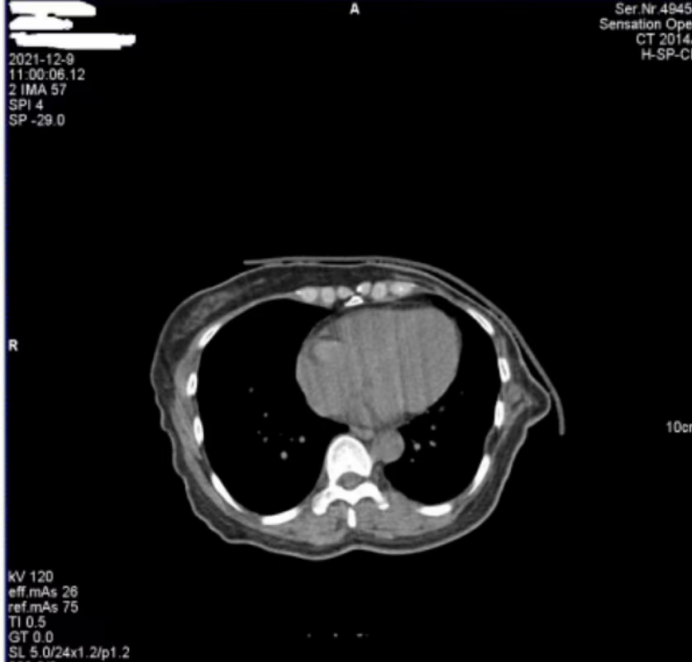

醫(yī)院反映,西門子Definition型CT機(jī)在進(jìn)行患者掃描時(shí),圖像上會(huì)偶發(fā)兩種偽影。一種是斜線狀偽影(圖 1),另一種是中心不規(guī)則高密度偽影(圖 2)。其中,斜線狀偽影對(duì)診斷影響較大,時(shí)常導(dǎo)致醫(yī)生無法準(zhǔn)確判斷患者病灶情況,醫(yī)院希望我們盡快排查并解決問題。

圖1

對(duì)于圖 1 中的斜線狀偽影,我們第一時(shí)間查看了設(shè)備的錯(cuò)誤日志和球管歷史記錄,然而并未發(fā)現(xiàn)球管存在打火情況的相關(guān)信息。但仔細(xì)觀察圖 1 中的 S35C0,結(jié)合我們多年的維修經(jīng)驗(yàn),這一參數(shù)特征明確指向在當(dāng)時(shí)的掃描曝光時(shí)刻,球管存在打火現(xiàn)象。球管打火會(huì)直接干擾射線的穩(wěn)定輸出,進(jìn)而在圖像上形成這種斜線狀偽影,這也解釋了為何該偽影會(huì)對(duì)診斷造成較大影響。

綜合以上分析,圖 1 中的斜線狀偽影由球管打火引起,且已嚴(yán)重影響診斷;圖 2 中的中心偽影雖成因未完全確定,但推測(cè)與球管內(nèi)部雜物有關(guān)。鑒于球管打火問題的嚴(yán)重性以及兩種偽影可能存在的關(guān)聯(lián)性,我們判斷需要更換球管來徹底解決問題。

此次維修案例中,更換球管后兩種偽影均消失的結(jié)果,不僅證實(shí)了圖 1 中斜線狀偽影由球管打火導(dǎo)致的判斷,也驗(yàn)證了我們對(duì)圖 2 中心偽影成因的推測(cè)是正確的,即球管內(nèi)部雜物在油路循環(huán)過程中,于曝光時(shí)處于出射線位置而造成了中心偽影。